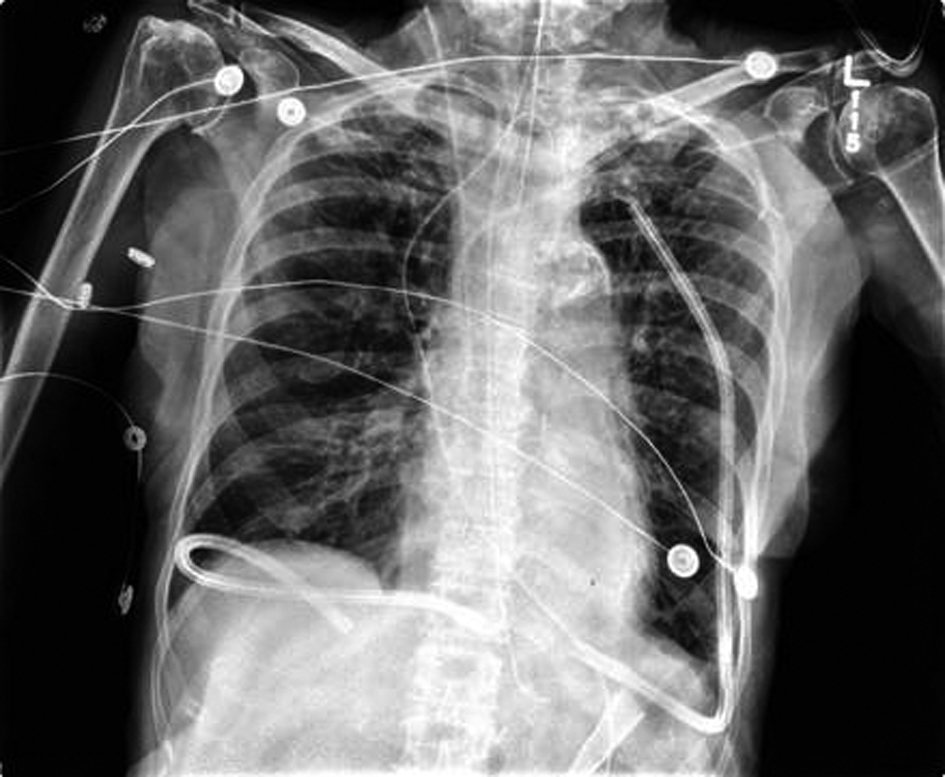

The patient underwent a THE as well as placement of a feeding jejunostomy tube. As per our standard practice, Jackson-Pratt (JP) drains were placed in the pleural spaces bilaterally via the mediastinal hiatus to prevent the collection of any possible post-operative effusions (Fig. 1). The patient tolerated the procedure well but post-operatively the patient deteriorated into respiratory failure requiring re-intubation and transient vasopressor support. By the third post-operative day, a second attempt of extubation had failed and the decision for early tracheostomy placement was made to assist with long-term ventilatory support. Slightly more than one week post-operative, the right thoracic JP drain was noted to be draining about 5 L of serous fluid daily. There was evidence of increasing right sided pleural effusions on chest X-ray (Fig. 2). Drainage continued at an average of more than 4 liters per day, with a peak output of nearly 6 liters at one measurement. As enteral feeds were initiated via the jejunostomy, it was noted the pleural effluent changed from serous to white, opaque, and fatty. The suspicion of chyle leak was confirmed with elevated triglyceride level from the draining fluid. As enteral feeds were stopped, JP output moderately decreased and again became transparent. Octreotide and parenteral nutrition were initiated for attempted conservative management of the chylothorax. This management failed, however, as the daily chylous thoracic output persisted at an average of more than 3 L per day. A lymphoscintigram failed to locate the specific source of the lymphatic leak therefore targeted embolization/ligation of the thoracic duct via interventional radiology was precluded.

![]() Click for large image | Figure 1. Immediate Post-operative Chest X-Ray following THE. |